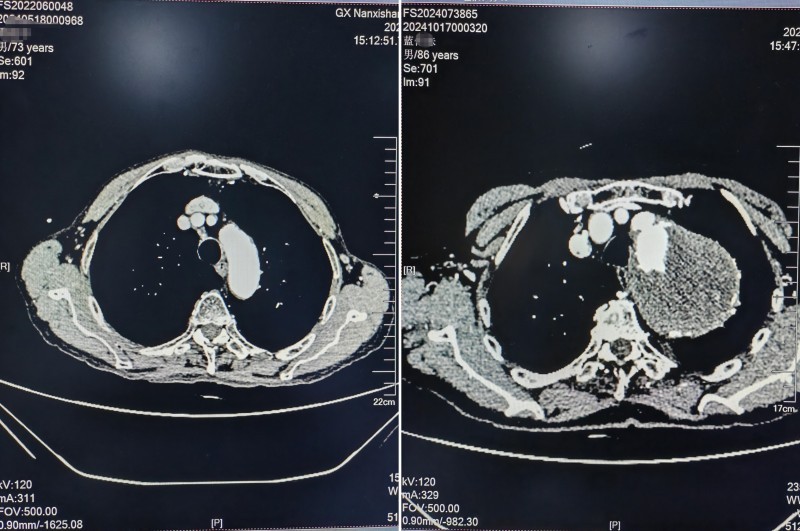

抵达南溪山医院时,蓝大爷的胸背部疼痛仍在持续发作。心脏大血管外科的值班医生迅速给予稳定血压、心率、止痛等对症治疗,待老人生命体征平稳后,进一步护送他进行主动脉夹层CTA检查。检查结果令人震惊:巨大胸主动脉瘤合并附壁血栓形成,动脉瘤直径竟达到82mm,远超正常范围。

面对如此巨大的动脉瘤和随时可能破裂大出血的风险,心脏大血管外科的医生们深知手术难度和风险之大。经过深入了解和讨论,医生们发现蓝大爷早在上世纪80年代就曾在胸片体检中发现左胸部有肿物,但因当时医疗条件有限且没有不适症状,一直未予重视。近年来,老人反复出现左侧胸背部疼痛,但总是自行通过“运功”调理,没有进一步就医。

图片3:正常主动脉与患者主动脉CTA